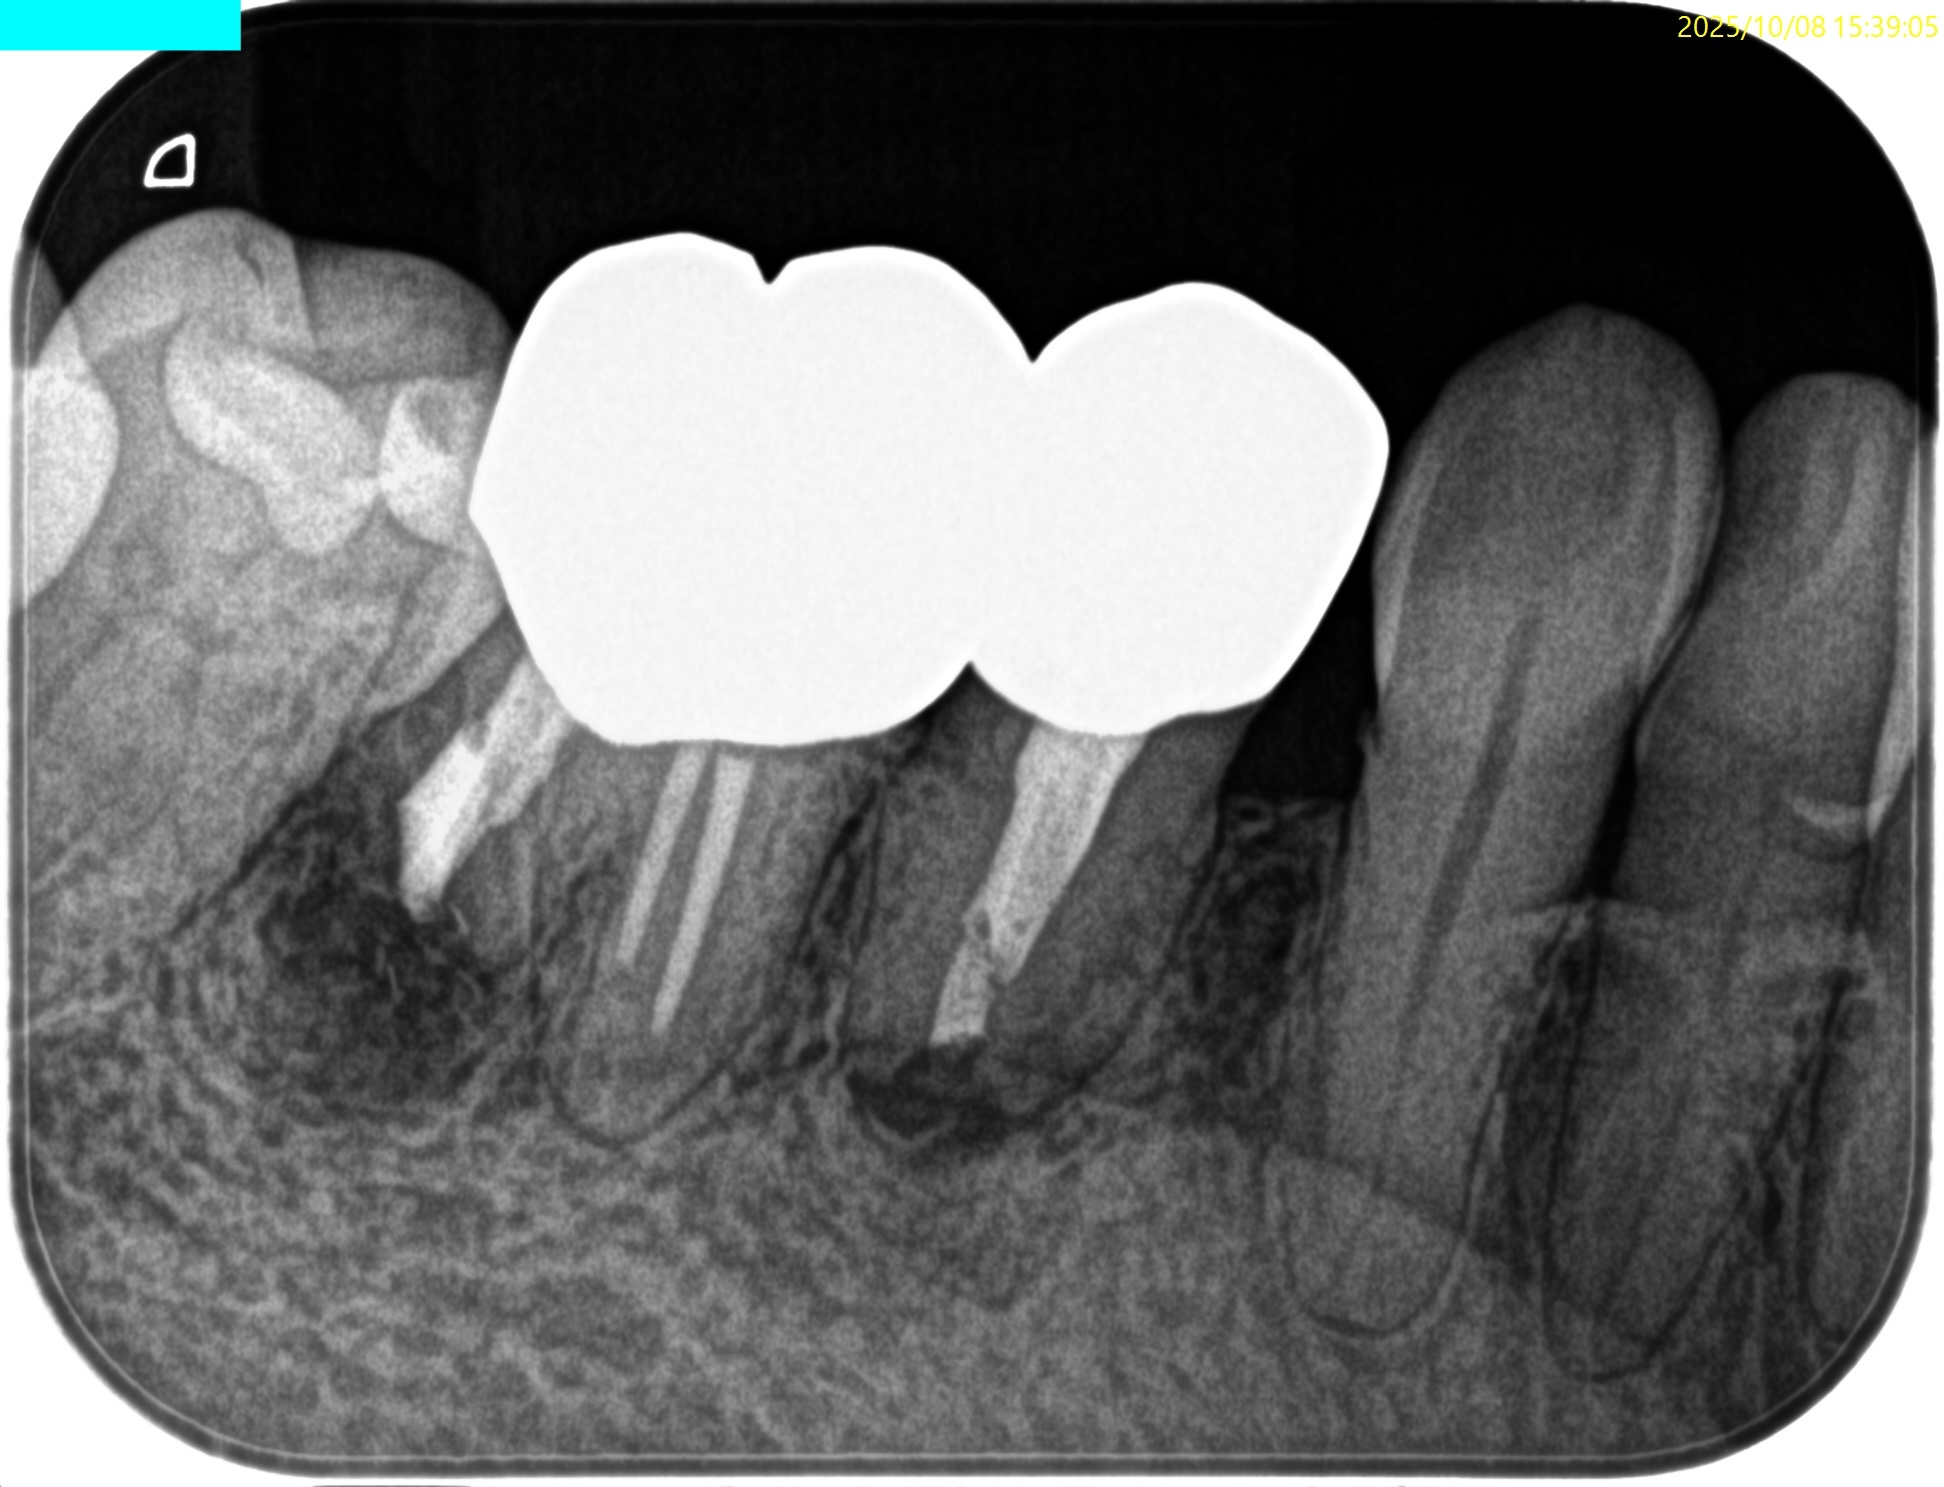

#30 D Apicoectomy(2025.10.8)

OsteotomyしてRoot resectionした。

Retroprepした。ここが一番時間がかかる。

逆根管充填した。

PA, CBCTを撮影した。

問題はないだろう。